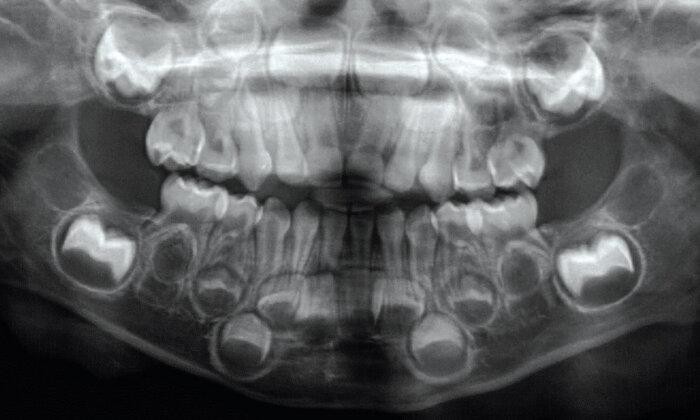

1. How old is the patient with the following X ray?